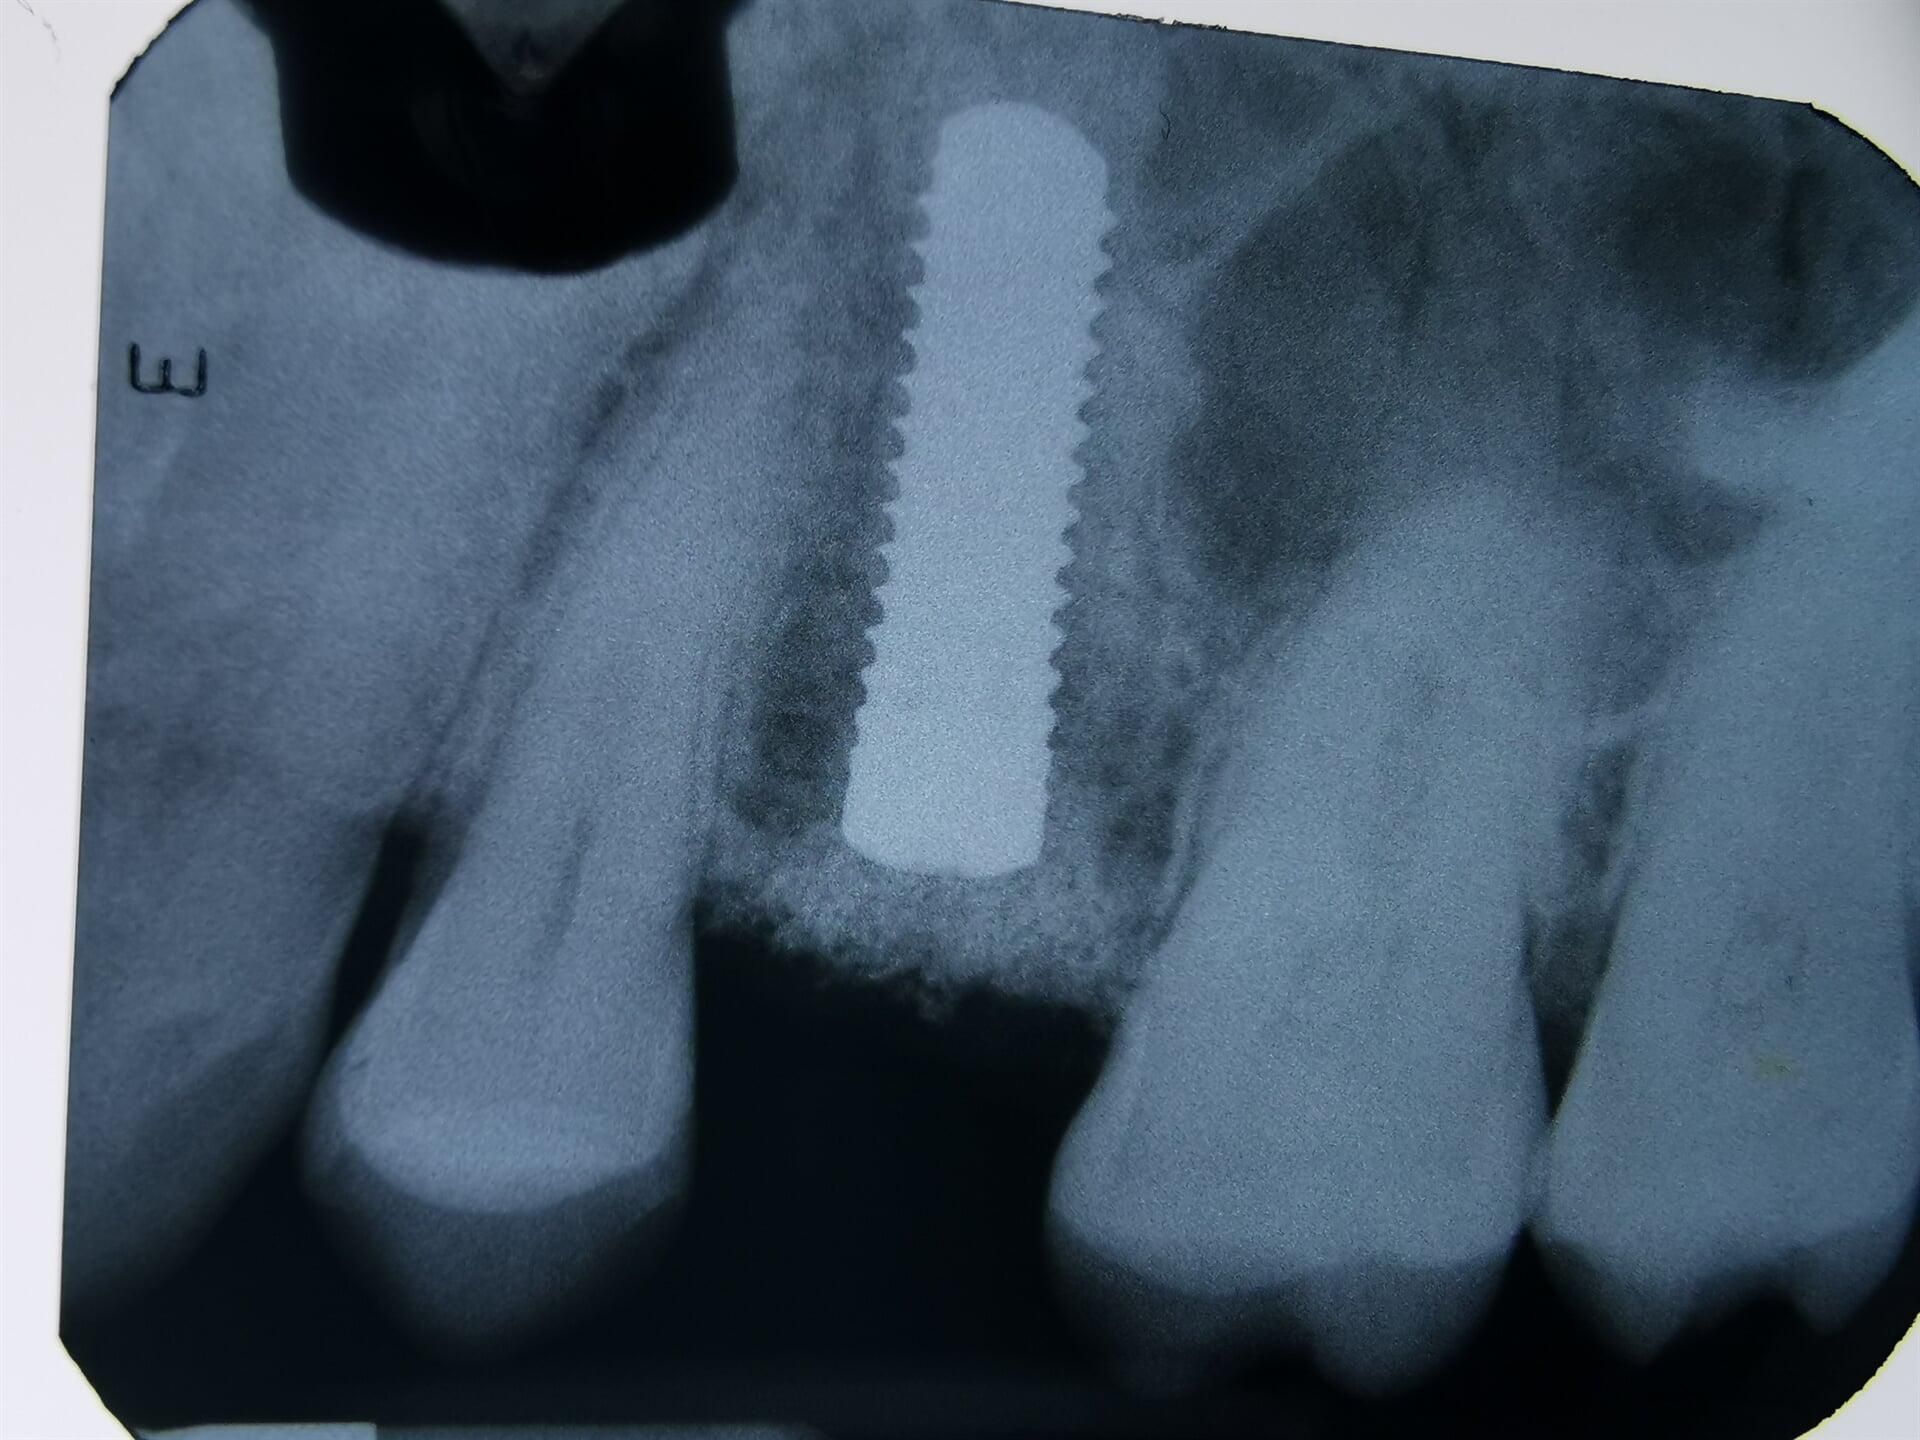

IMPLANTES

DENTALES

Antes de pensar en colocar un implante, primero deberemos realizarte una serie de estudios, así como valoración a detalle de tu cavidad oral para proponer que tratamiento es el ideal para ti.

En CIMOH contamos con equipo multidisciplinario para lograr evaluarte y decidir si eres o no candidato para este tipo de tratamientos, en caso de no serlo, también de sugeriremos diferentes opciones para tu rehabilitación.